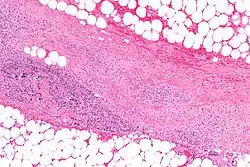

.webp.png)

Necrotizing fasciitis is ideally a clinical diagnosis based on symptoms. Due to the need for rapid surgical treatment, the time delay in performing imaging is a major concern.[15] Hence, imaging may not be needed if signs of a necrotizing infection are clear. However, due to the vague symptoms associated with the earlier stages of this disease, imaging is often useful in clarifying or confirming the diagnosis.[15]

Both CT scan and MRI are used to diagnose NF, but neither are sensitive enough to rule out necrotizing changes completely.[2]

Computed tomography (CT)

If available, computed tomography (CT) is the most convenient tool in diagnosing NF due to its speed and resolution (detects about 80% of NF cases).[16] CT scan may show fascial thickening, edema, or abscess formation.[2][15] CT is able to pick up on gas within tissues better than MRI, but it is not unusual for NF to present without gas on imaging.[15] In addition, CT is helpful in evaluating complications due to NF and finding possible sources of infections.[15] Its use may be limited in pregnant patients and patients with kidney issues.[15]